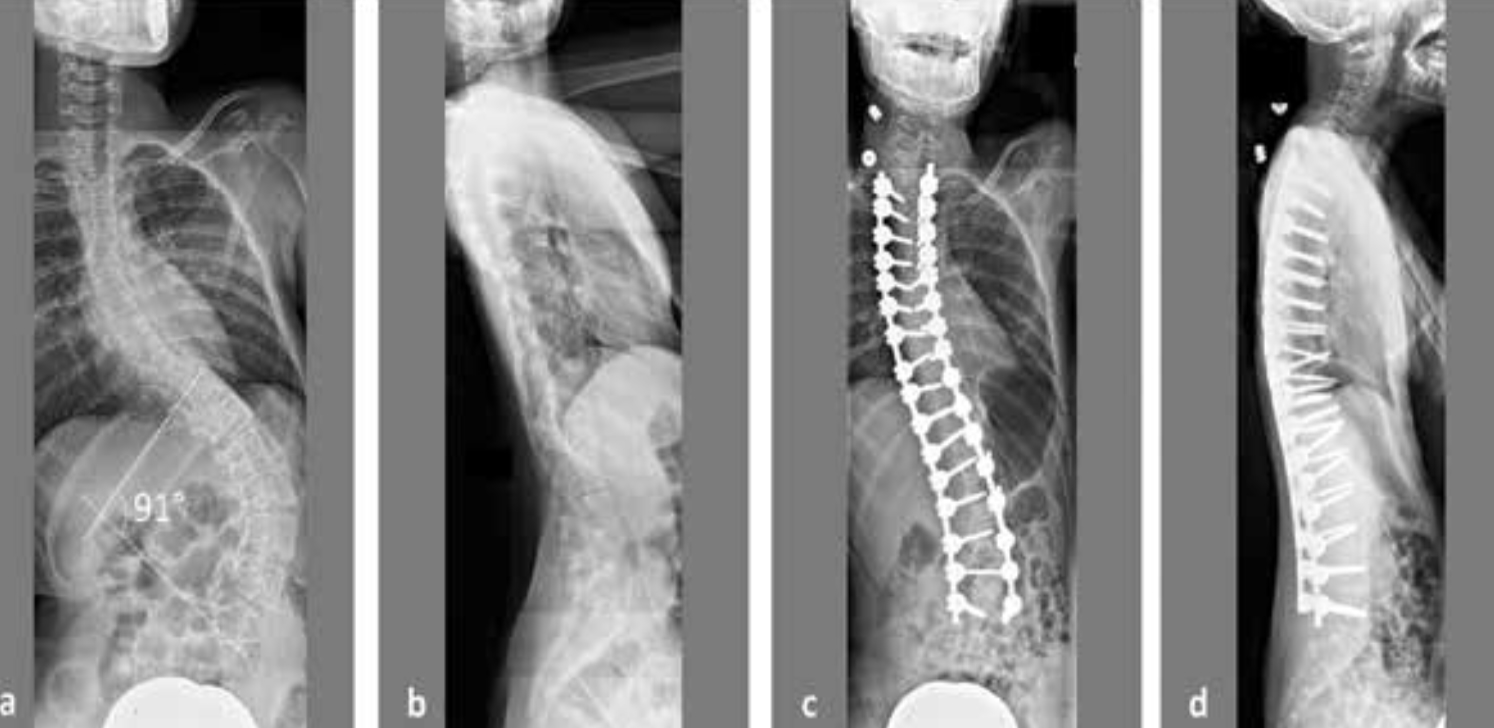

Did You Know the Varying Degrees of Scoliosis?

“Scoliosis can be a small curve. It can be a single curve, a double curve. It can be higher in the spine or lower in the spine. So it depends on the [individual] and how that person is growing.

It’s often driven by growth. So the occurrence is in about 3% of the population of that a small minority will end up having to have it treated. And we don’t treat curves, generally speaking, below 20 degrees, so there needs to be a size that the physician deems appropriate for bracing.”

Between 20 and 50 degrees is the range that’s often suggested for bracing. And above 50, surgeons start to talk about the need, potentially, for a surgical intervention for a fusion of the spine.”